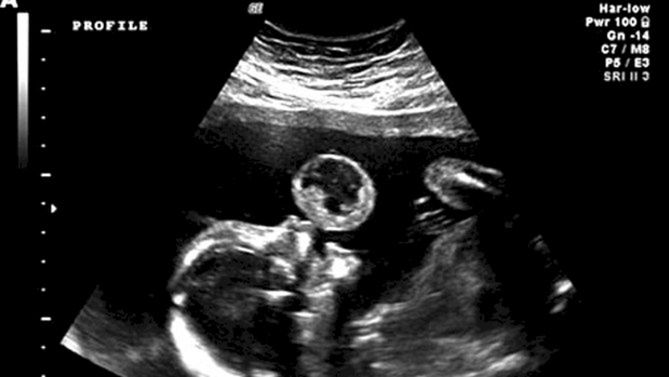

Tammy Gonazalez z Miami na Florydzie od jakiegoś czasu nosiła w sobie dziecko. Była szczęśliwą przyszłą mamą. W 17 tygodniu ciąży musiała udać się na rutynowe badania. W trakcie badania, na USG pojawiło się coś w rodzaju „bańki”. Wyglądało to, jakby dziecko w brzuchu mamy puszczało bańki lub robiło balony z gumy. Jednak wyobraźnia niestety nie miała tutaj nic wspólnego z rzeczywistością.

Lekarze byli również zaskoczeni dziwnym obrazem USG. Szybko zlecili kobiecie dodatkowe badania. Okazało się, że „bańka” to jeden z bardzo rzadko spotykanych nowotworów. Diagnozą był potworniak, który jest zmianą o torbielowatej budowie.